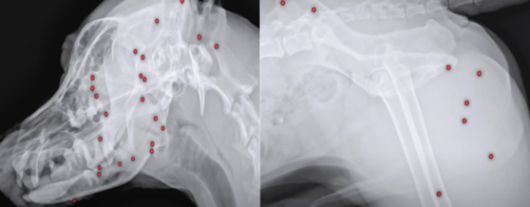

지난 4월 구조 후 해외 입양을 위해 건강검진을 받으려던 유기견 '귀동이' 몸속에서 산탄총 파편 70여 개가 발견됐다. 〈사진=VIP동물의료센터 유튜브 영상 캡처〉 |

지난 4월 구조된 8~9살로 추정되는 수컷 유기견 '귀동이'의 엑스레이 사진입니다. 몸속 곳곳에 작은 물체가 다닥다닥 박혀 있습니다. 다름 아닌 산탄총 파편으로 무려 70여개에 달합니다.

오늘(25일) VIP동물의료센터에 따르면 반려동물돌봄전문단체 도그어스플래닛은 지난 4월 백구 '귀동이'를 구조한 뒤 해외 입양을 위한 건강검진에 나섰다가 귀동이 몸속에 70여개의 산탄총 파편이 박혀 있는 걸 확인했습니다.